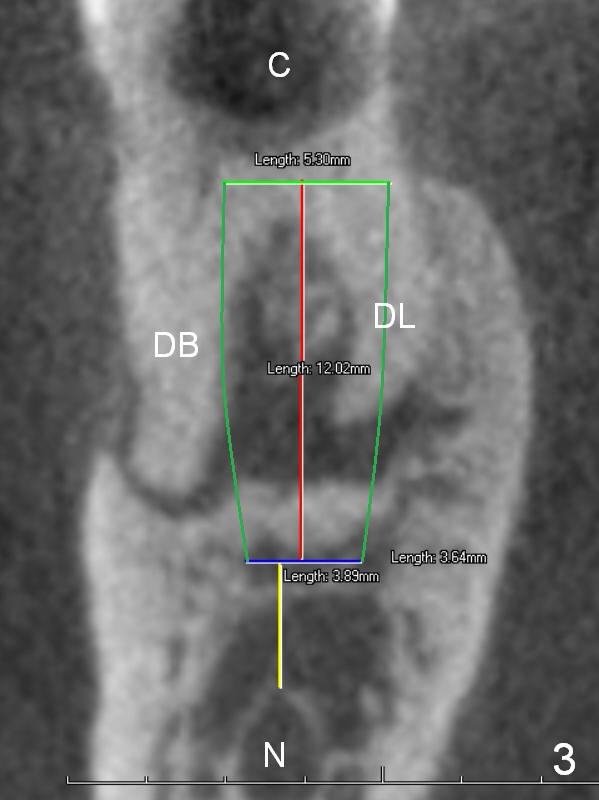

A 68-year-old lady (WQ) had CT taken 3 years ago (Fig.1-3), which show 3 roots (M: mesial; DB: distobuccal; DL: distolingual) of the lower right 1st molar and large caries (C).  Recently the tooth fractures after root canal therapy (Fig.4-6).

Having 3 roots suggests a tripod septum.  Surgical handpiece and elevators may be required, in addition to proximators.  Cowhorn forceps should be helpful.  The socket will be treated with Clindamycin, selected by time sequence.

An implant placed the tripod septum should be stable.  The length of the initial osteotomy is 12 mm using 2 mm pilot drill.  Take intraop PA as early as possible for trajectory and depth determination.